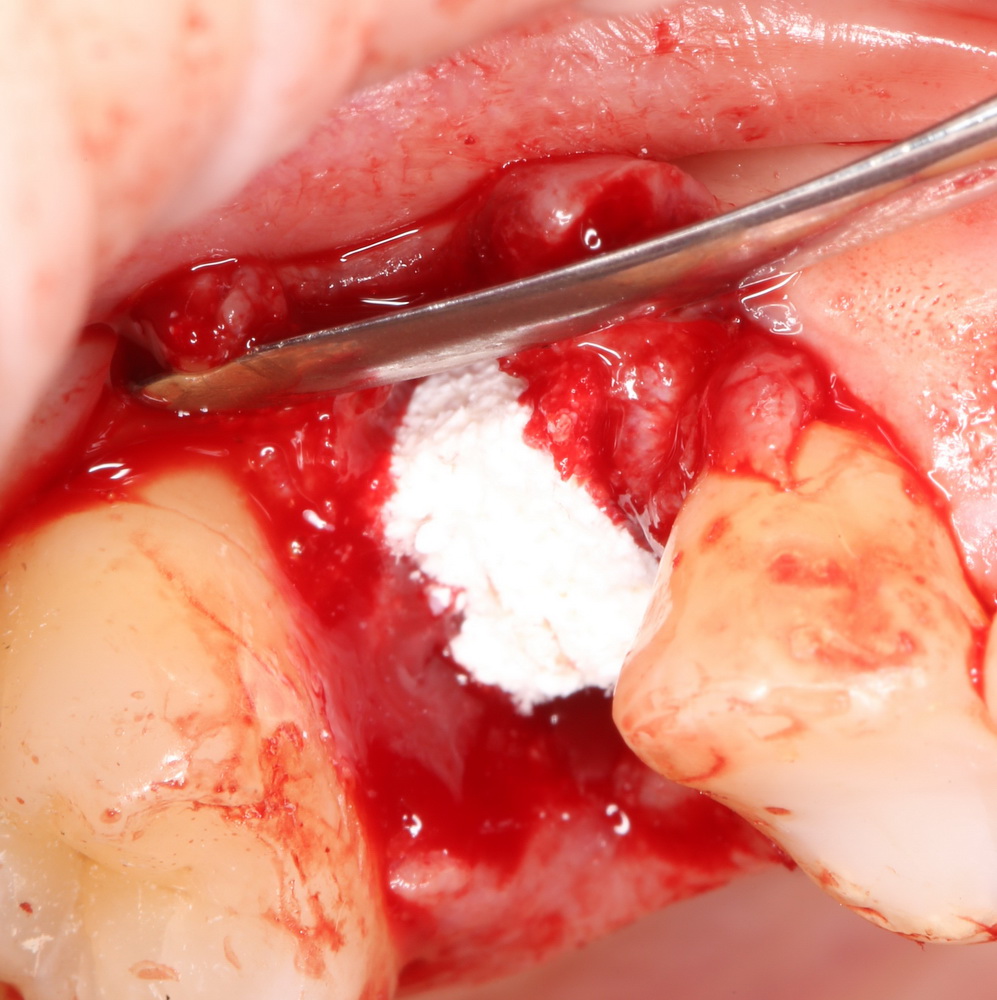

Графт адаптируется (с помощью скальпеля), устанавливается в нужное положение. Для этого, опять же, очень удобно использовать аналоги имплантов из имплантологического набора (в крайнем случае, остеотомы или пины параллельности):

Напомню, нет необходимости заполнять графтом всю лунку. Тем более — полость удаленной кисты или гранулемы. Поэтому 100 мг вполне хватает, чтобы аугментировать лунку любого объема.

Благодаря своим свойствам. Bio-Oss Collagen не забивается в подготовленную лунку импланта, не съезжает и не сползает при его установке:

Вот, собственно, и всё. Далее, наш биоматериал ведет себя совершенно также, как и обычный Bio-Oss — он быстро пропитывается кровью и отлично удерживается на месте:

Для аугментации также используем Bio-Oss Collagen 100 mg, нарезаем его по размеру с помощью скальпеля и позиционируем в лунках щечных корней: